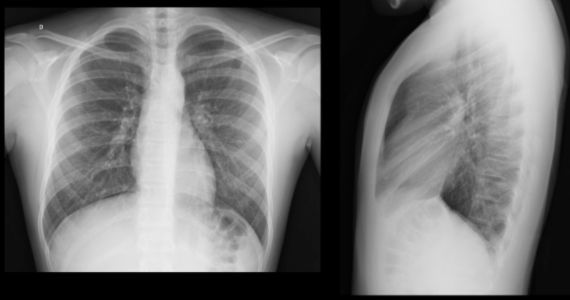

Dona Ana Cláudia, 32 anos, previamente saudável, apresenta história de dor precordial de início há 24 horas, de forte intensidade, a qual piora com a respiração, deglutição e ao se deitar. A dor irradia para o pescoço e ombro (em especial para as bordas do músculo trapézio). Relata que a queixa é constante e não se relaciona com esforço, além de não aliviar com dipirona 500 mg. EF: eupneica, normocorada e afebril. Pressão arterial: 142x82 mmHg, FC: 106 bpm, FR: 15 rpm, temperatura axilar de 37,1ºC e saturação de 95% em ar ambiente. Os marcadores de necrose (0- 6-9 horas) apresentaram discreta elevação. Eletrocardiograma e raios X do tórax, a seguir.

Assinale a alternativa CORRETA para o tratamento inicial proposto para Ana Cláudia.